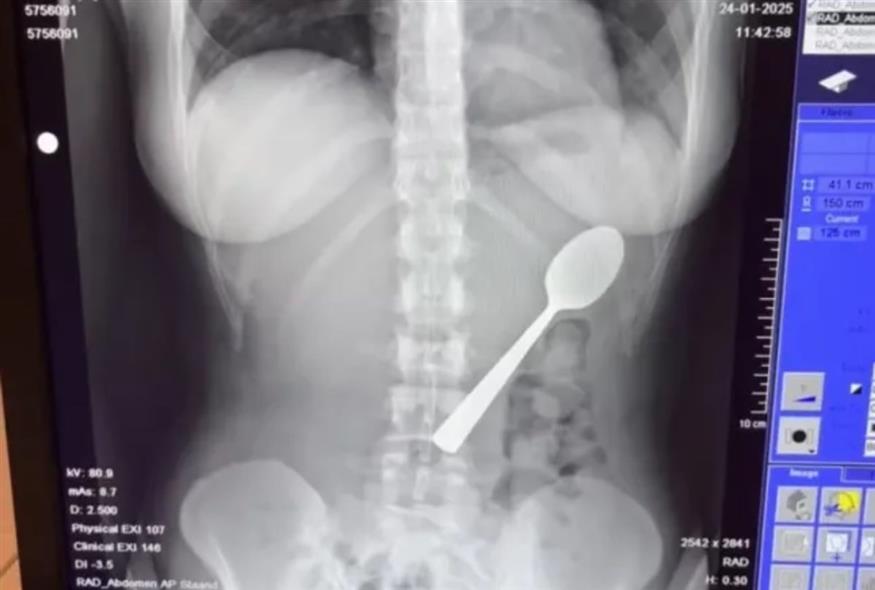

Πώς 28χρονη έφαγε κουτάλι 17 εκ. αντί για γιαούρτι - Τι συνέβη στο στομάχι της

Η Ρέιμι Άμελινξ δεν το έκανε, το κράτησε στο στόμα της περισσότερη ώρα για να απαντήσει σε ένα μήνυμα και βρέθηκε να καταπίνει ένα κουτάλι 17 εκατοστών, μια εμπειρία διόλου ευχάριστη αν και η ίδια παραδέχθηκε ότι «γλίστρησε πολύ ομαλά στο στομάχι μου».

Οι γιατροί της είπαν ότι το κουτάλι ήταν πολύ μεγάλο για να βγει... φυσιολογικά, οπότε έπρεπε να επιστρέψει σπίτι και να περιμένει μέχρι να προγραμματιστεί γαστροσκόπηση.

Δύο ημέρες αργότερα, η Ρέιμι ξύπνησε μετά την αναισθησία χωρίς κουτάλι μέσα της. «Οι γιατροί έπρεπε να το περιστρέψουν στο στομάχι μου, κάτι που προκάλεσε μια μικρή γαστρική αιμορραγία, αλλά ένιωσα μεγάλη ανακούφιση όταν βγήκε».